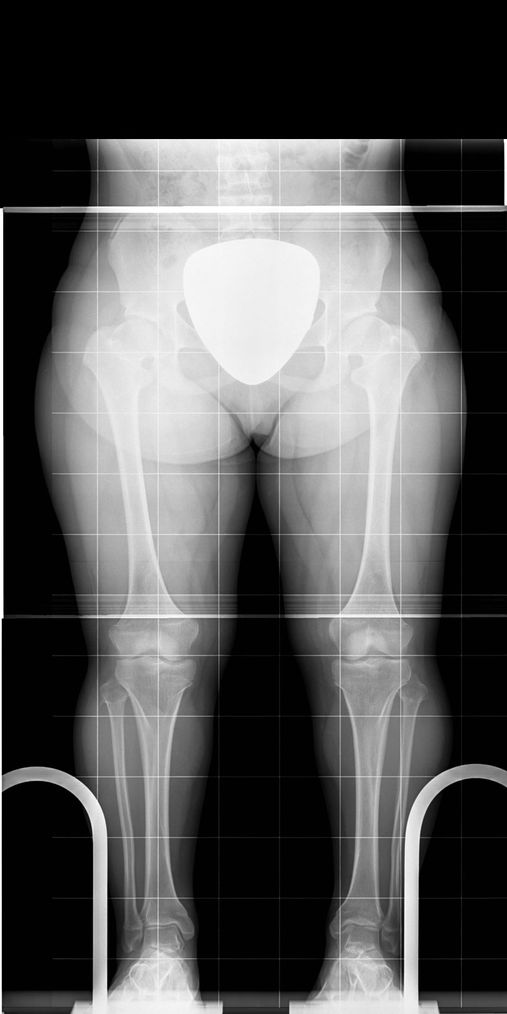

Kleinwüchsige Patientin mit Achondroplasie

Vor der Behandlung

Simultane Ober- und Unterschenkelverlängerung

Nach Abschluss der Behandlung

Um eine Vergrößerung von 15 cm und mehr zu erreichen, sind Verlängerungen beider Ober- und Unterschenkel erforderlich. Auch O- oder X-Beine können mit korrigiert werden. Was früher nur mit externen Fixateuren möglich war, kann man heute wesentlich schonender und vorteilhafter mit voll implantierbaren Distraktionsmarknägeln korrigieren.